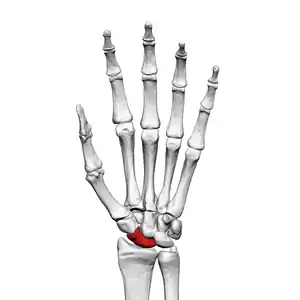

The scaphoid bone is one of the carpal bones of the wrist. It is situated between the hand and forearm on the thumb side of the wrist (also called the lateral or radial side). It forms the radial border of the carpal tunnel. The scaphoid bone is the largest bone of the proximal row of wrist bones, its long axis being from above downward, lateralward, and forward. It is approximately the size and shape of a medium cashew nut.

The scaphoid is situated between the proximal and distal rows of carpal bones. It is located on the radial side of the wrist,[1]: 176 adjacent to the styloid process of the radius.[2] It articulates with the radius, lunate, trapezoid, trapezium, and capitate.[1]: 176 Over 80% of the bone is covered in articular cartilage.[3]

The carpal bones function as a unit to provide a bony superstructure for the hand.[5]: 708 The scaphoid is also involved in movement of the wrist.[1]: 6 It, along with the lunate, articulates with the radius and ulna to form the major bones involved in movement of the wrist.[5] The scaphoid serves as a link between the two rows of carpal bones. With wrist movement, the scaphoid may flex from its position in the same plane as the forearm to perpendicular.[1]: 176–177